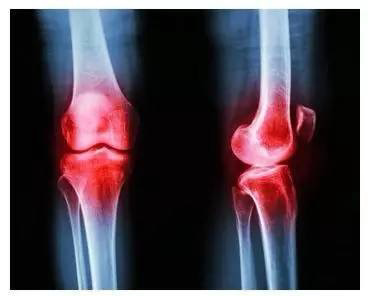

【胃癌|治骨关节病,先调气血!气血与骨骼密切相关】对于骨关节病 , 一般大多数人认为其病因在骨 , 只要治疗骨头问题就行 , 其实 , 中医角度认为骨关节病发病机理多与气血相关 , 与肝肾虚衰相关

中医认为 , 骨关节病多与肝肾气血相关 , 因经络瘀滞所致 , 治疗应多已祛风寒湿邪 , 只有祛除病邪 , 才能使气血调和 , 肾气得养 , 骨脉得充 , 疾病方可痊愈 。 骨关节病多发于中老年人 , 其原因就是因为人到中年后 , 肝肾开始虚衰 , 气血有所不足 , 人的活动能量有所减少 , 加之外受寒邪湿气 , 客于骨髓 , 所以造成骨病

而肝肾虚弱 , 气血不足 , 风寒湿邪趁虚侵袭机体 , 流注经络 , 导致气血运行不畅 , 从而导致脊柱附近的颈骨关节肌肉和颈腰背神经支配的肢体出现 , 酸 , 麻 , 沉 , 痛 , 木以及活动受限

中医讲 , 肝主筋藏血 , 肾主骨生髓 , 因此 , 人步入中年以后 , 肝血肾精衰少 , 骨髓生化乏源 , 髓精不足 , 不能濡养筋骨 。 督脉失养亦可以造成颈椎 , 腰椎发生退行性病变 , 出现筋骨萎弱 , 从而形成退行性骨变

气血虚弱 , 风寒湿邪侵袭机体 , 表现为肢体关节疼痛 , 屈伸不利 , 冬天阴雨天易发作 , 得温痛减 , 遇冷则加重 , 久而久之就形成了严重了骨关节病

治风先治血 , 血行风至灭 。 气血不通容易引起骨关节病变 , 其原因就是因为骨关节处的血运相比其他部位较为薄弱 , 人的关节部位是最容易缺少气血的部位 , 所以治疗补气血 , 补肝肾 , 是治疗骨关节病的根本所在 。